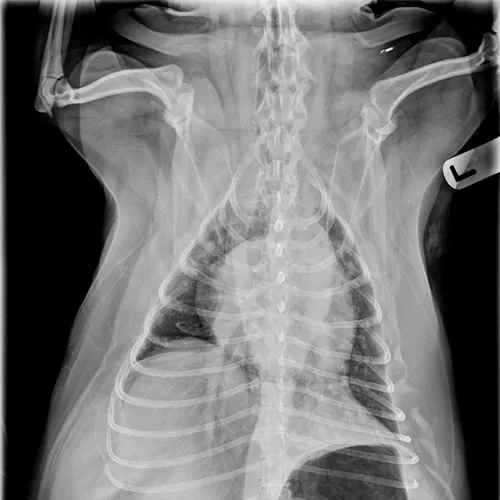

Dogs with bacterial pneumonia are typically presented with acute-onset coughing, lethargy, inappetence, and/or respiratory distress. An inflammatory leukogram and pyrexia, although common, are not always present. Radiographs may reveal an interstitial-to-alveolar pattern with a cranioventral distribution (Figure 1). Atypical distributions can also occur.5

FIGURE 1

(A) Bronchopneumonia. Cranioventral distribution of alveolar disease with air bronchograms. (B) A patchy distribution can be observed on the lateral projection. The changes overlying the heart may be missed in subtle cases.